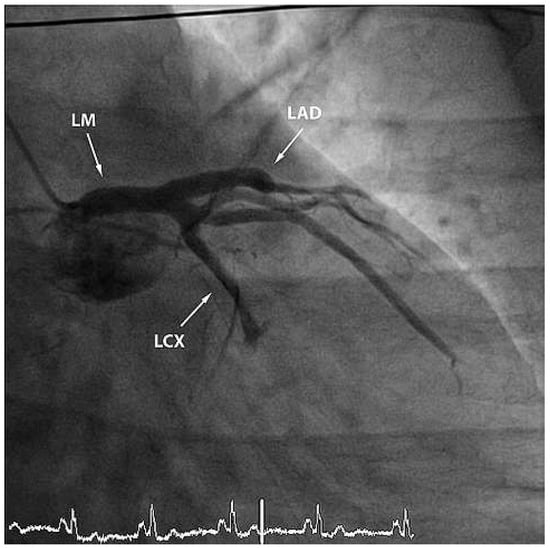

Furthermore, the right coronary artery showed a subtotal thromNo botic occlusion (Figure 3). Prior to the local treatment, a bolus of heparine 5000 IU and Abciximab were administered due to the heavy thrombus load. Thrombus aspiration was performed using an aspiration-catheter (Export AP, Medtronic) in all three coronary vessels. Due to persistent thrombotic material in the mid LAD, two low-pressure balloon inflations were done with a good end result (Figure 4 and Figure 5). There were no periprocedural complications. A treatment with life-long aspirin, one-year prasugrel, Betablocker and ACE-Inhibitor was initiated. The next day, a transesophageal echocardiography demonstrated improved LV-function (EF 50%) without evidence for an intracardiac thrombus or a patent foramen ovale (PFO).

Figure 4. RAO view showing good end result after thrombus aspiration in LAD and RCX and PTCA of the LAD.